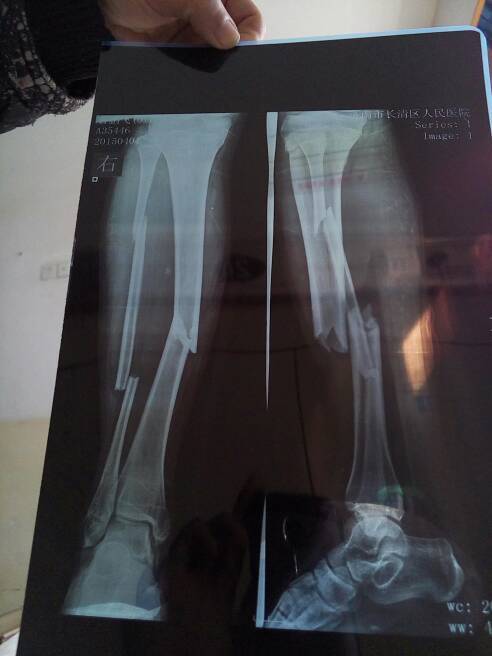

小腿骨折,住院8天后,小腿筋疼怎么办? 小腿骨折,住院8天后,小腿筋疼。怎么办? 点击展开 菲芘 梦琪 2015-04-09 14:41 为您推荐: 其他回答 问问医生最好 幸福两口子_SpYD 2015-04-09 14:57 骨折的治疗方法很多,轻微的骨折一般需用石膏或夹板外固定,严重时需采用手术,用钢板或钢针内固定,这样有利于疾病的治疗。 具体需根据骨折的严重程度分析,针对性的使用药物来治疗,都可以逐渐好转或痊愈的。 ־ҽ 2015-04-09 14:42 相关问题 小腿骨折好后走路筋痛 3岁小孩小腿骨折,未伤到筋会不会留下后遗症? 左小腿骨折手术后松筋草煮水可以洗脚吗